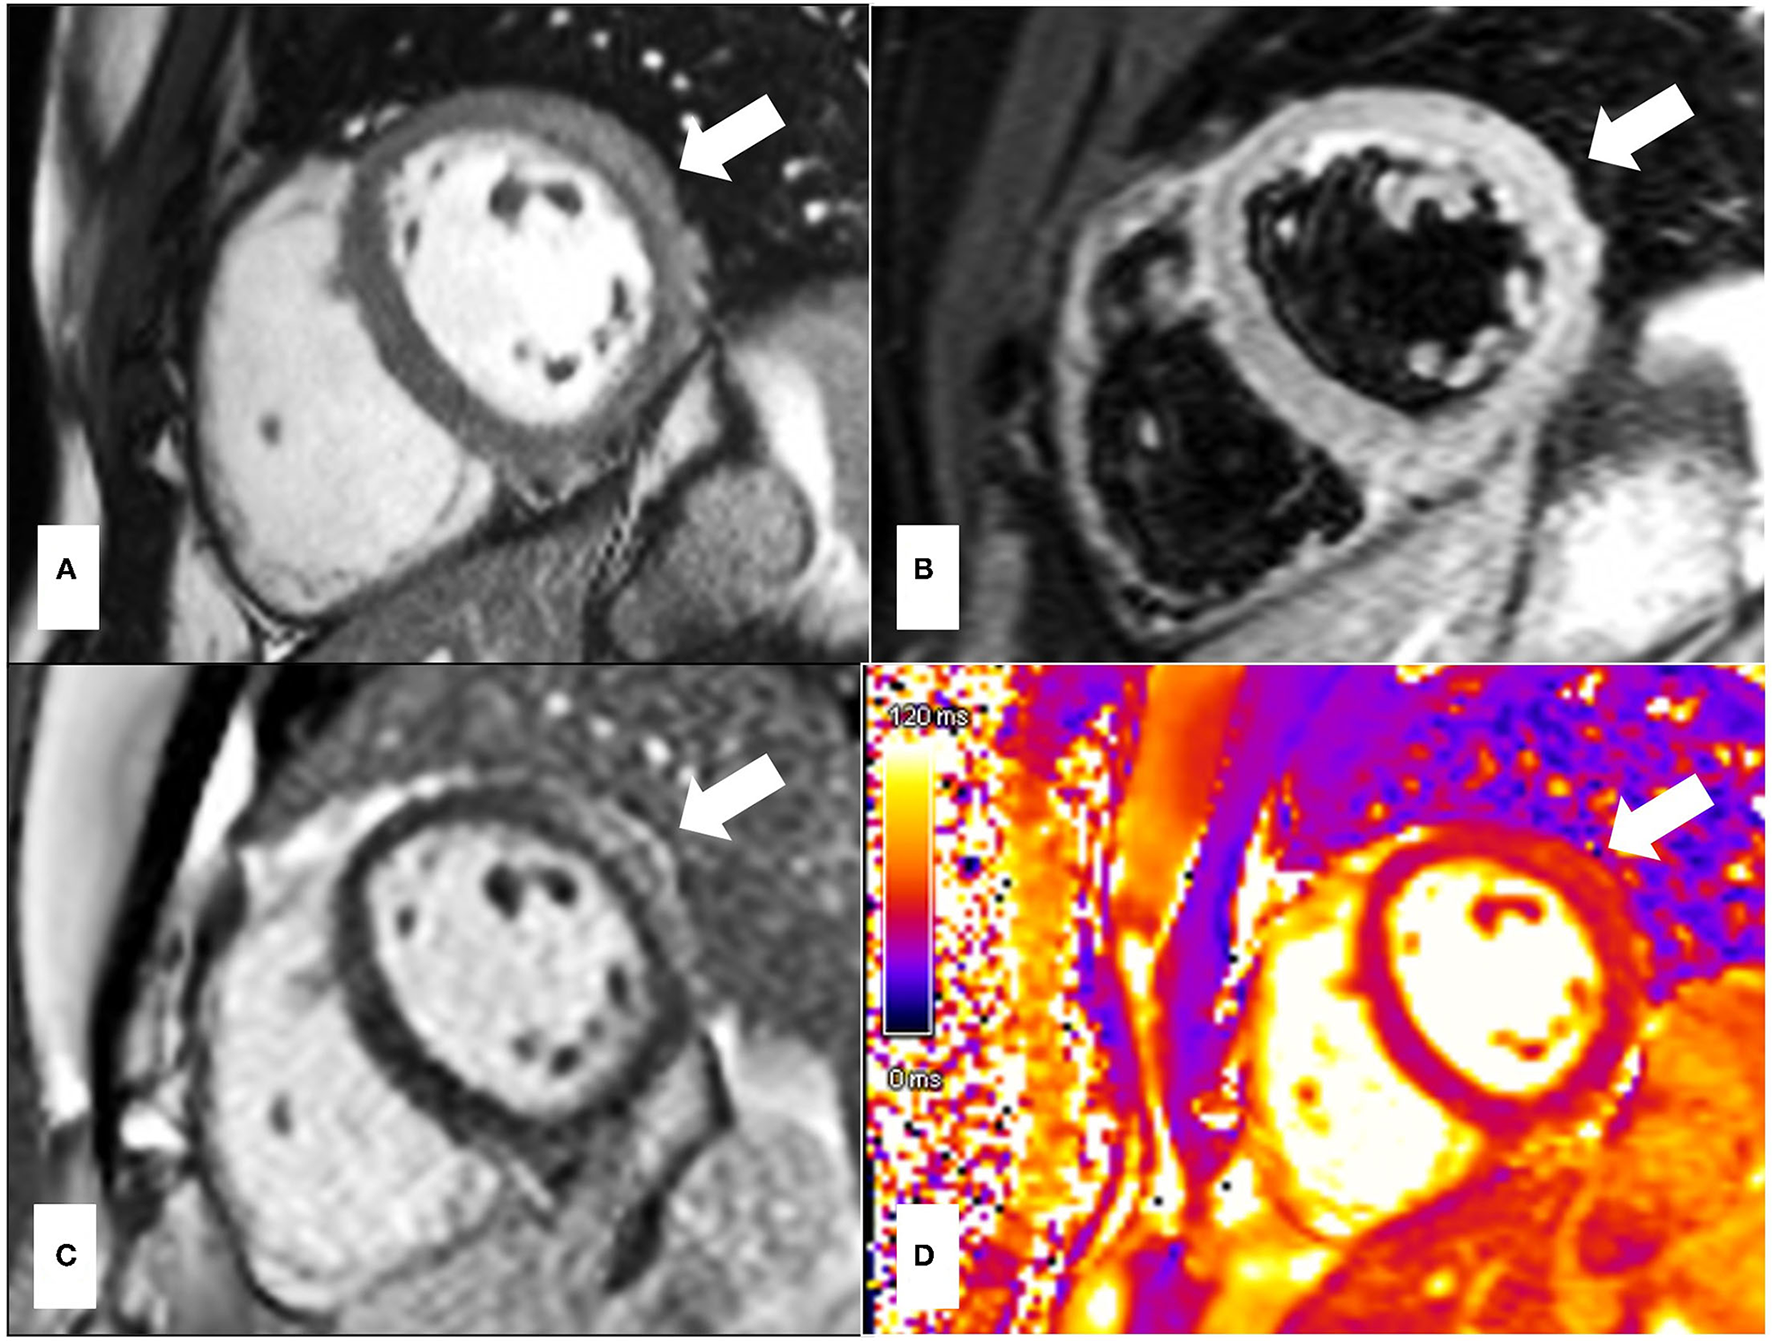

CMR findings are similar in patients with MINOCA in comparison to those with MI-CAD (Figure 1). Multi-modality imaging and an integrated approach should be considered in all cases where the final diagnosis remains unclear.

Figure 1

74-year old male presented with chest pain and troponin rise with lateral T-wave inversion on electrocardiogram. Invasive coronary angiography demonstrated non-obstructed coronary arteries. CT pulmonary angiography was also negative for pulmonary embolus. A Cardiac MRI demonstrated evidence of myocardial infarction with typical ischemic pattern of subendocardial late gadolinium enhancement (LGE) [white arrows, (A1–A3): 4 Chamber, 2 Chamber, 3 Chamber, (B) short axis] in the apical inferior and lateral segments. Areas of high signal on T2-STIR imaging (C) and T2-mapping (D) correlating to the area of infarction from LGE imaging and the ECG abnormalities, suggesting acute myocardial edema due to acute myocardial injury.